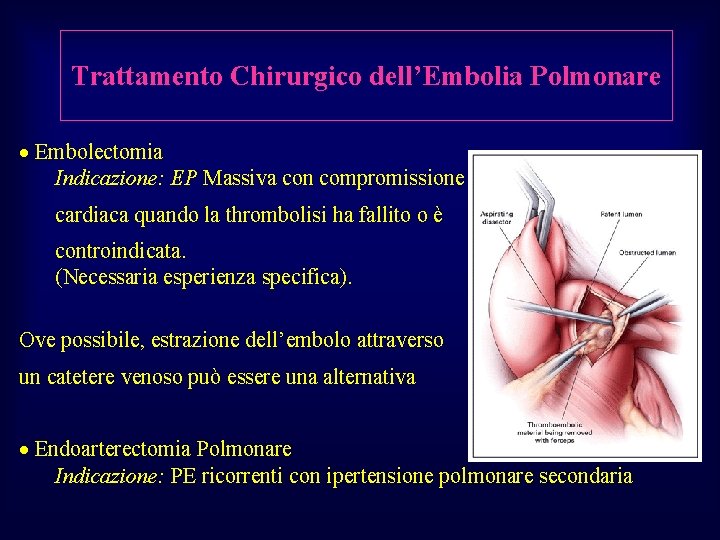

Trattamento Chirurgico dell’Embolia Polmonare · Embolectomia Indicazione: EP Massiva con compromissione cardiaca quando la thrombolisi ha fallito o è controindicata. (Necessaria esperienza specifica). Ove possibile, estrazione dell’embolo attraverso un catetere venoso può essere una alternativa · Endoarterectomia Polmonare Indicazione: PE ricorrenti con ipertensione polmonare secondaria